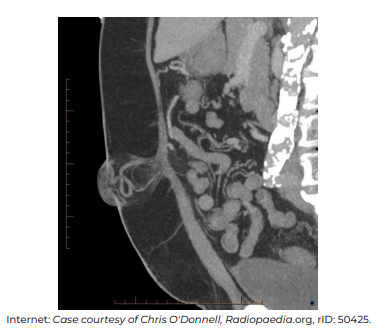

No que diz respeito à interpretação e ao diagnóstico nosológico que explica os achados na imagem apresentada, assinale a alternativa incorreta.

No que diz respeito à interpretação e ao diagnóstico nosológico que explica os achados na imagem apresentada, assinale a alternativa incorreta.